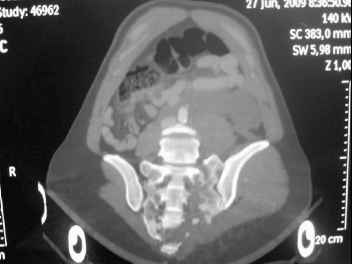

I'm posting this case on behalf of Dr. Pedro Caba, he is unable to post but able to read. 41 yo female , fall from 10 meters five days ago. Hemodynamically unstable on admission treated by angio and embolization and skeletal traction, with no external support. No associated injuries. Based on CT scan the pt has a both column fracture with conminuted dome and displaced anterior column and a sacral Denis 1 fracture with a displaced left ala. I think the best approach for the acetabular fracture is ilioinguinal with Smith-Petersen extension but don't know exactly the sequence . Will you start with the sacral fracture? Which technique? Thanks in advance Pedro Caba Unidad de Trauma Hospital 12 de Octubre Madrid Spain

The soft tissues are also in mild condition, buttock hematoma and probably a Morel-Lavalle. I send some more CT images. There are some conminution in the posterior column (I don’t have images now). The patient is scheduled for surgery next Monday. The plan is percutaneous sacral fixation and then ilioinguinal approach .